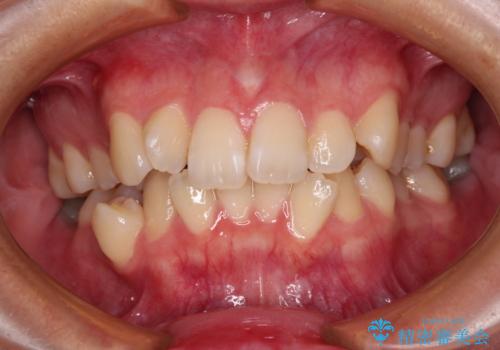

受け口と八重歯を改善 インビザライン矯正治療